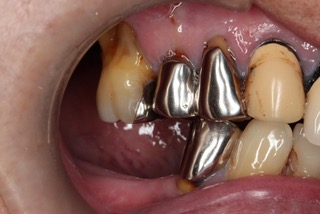

右側 before

右側 after